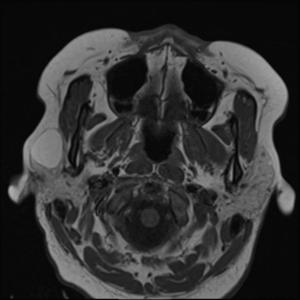

Image IQ: Right Face Swelling

Patient presents with right facial swelling.